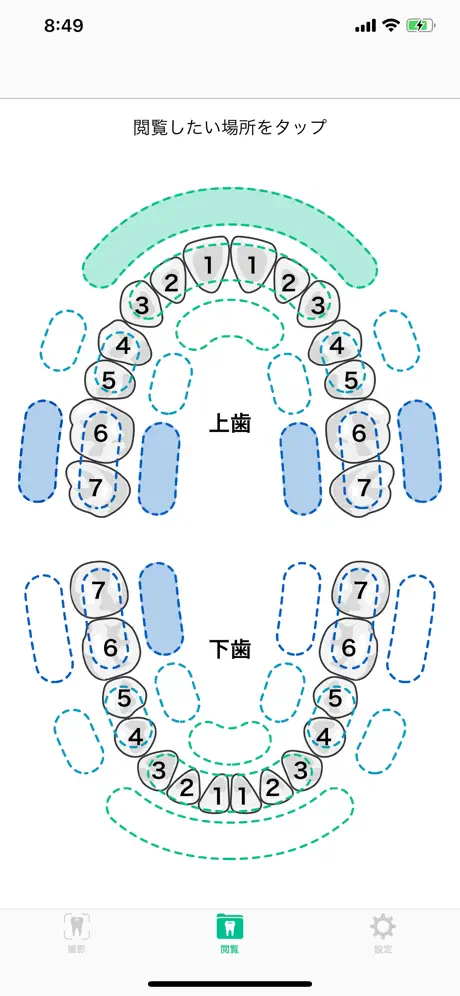

Screenshots